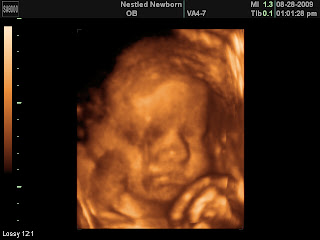

We had a 3-D ultrasound and Ellie was a little stubborn. I think she may get this trait from her Daddy! She had her hands in her face most of the time, but we were able to get a few pictures. The ultrasound tech reconfirmed she was a girl (thank goodness), that she has some hair, and some chubby cheeks! She told us that in the last few weeks, she had two couples come in thinking they were having a girl and it was definitely a boy! They were both 30 weeks. We can't wait to meet this little miracle in less than 11 weeks!

2. love those chubby cheeks!! AND....the last pictures looks like a papparazzi pose. ;) love to you all!!